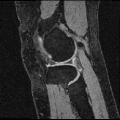

We applied AutoReg to a wide range of MRI registration scenarios from mono-modality (registering brain T1 images to an averaged T1 template, brain T1 to T1 images, brain T2 to T2 images, knee T1 to T1 images, and lung CT inspiration to expiration images) to multi-modality (registering brain T1 to T2 images, brain T2 to T1 images).

Knee T1-to-T1 registration. We employ knee MRIs from the Osteoarthritis Initiative 444https://nda.nih.gov/oai/ with corresponding segmentations of femur and tibia as well as femoral and tibial cartilage [49]. We divide images into 377, 21 and 130 volumes for training, validation and testing. All images are resampled to isotropic spacing of 1mm, in size of .

Table. IX demonstrates performance in terms of Dice score on challenging registration tasks, including brain T1 MR image-to-image, brain T2 MR image-to-image, multi-modal (including T1-to-T2 and T2-to-T1), and knee T1 MR image-to-image registrations. While our method gives an obvious lower variance with a comparable Dice for all of these cases. Fig. 6 depicts the stability of the methods in view of the box-plot of Dice score, where fewer outliers and lower variance indicate a more stable registration. Note that, the optimization-based methods perform slightly better for the brain registration where the image pairs are much more similar to each other. However, they are less satisfying in the knee T1-to-T1 registration. When faced with such various challenging cases, learning-based models struggle to provide comprehensive solutions. While our method gives an obvious lower variance with a comparable mean of Dice for all these cases, showing stronger stability.

Our representative registration results are given in Fig. 7 and Fig. 8. The first three registration cases in Fig. 7 contain image-to-atlas on T1 brain MR, image-to-image on T1 brain MR and T2 brain MR test pairs. The large deformations in scans make registration challenging and difficult. As a result, all the source images are well aligned to the target. The second three rows in Fig. 8 contain knee T1 MR data, multi-modal data, and lung CT inspiration-expiration images. Although large deformations and intensity differences exist in scans, source images are well aligned to the target, demonstrating our outstanding performance.